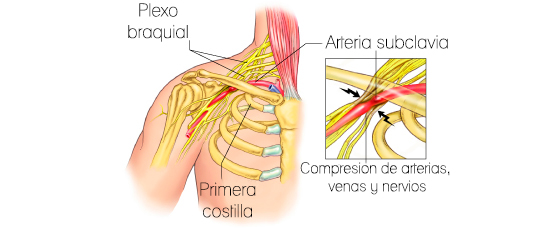

Síndrome de la salida torácica (TOS)

TOS es una condición que resulta de la compresión de los nervios, arterias y venas a medida que pasan a través del cuello al brazo (salida torácica). Posibles causas como los músculos escalenos apretados y músculos pectorales, costilla cervical extra, y prolongada duraciones de trabajar con los codos elevados. Este trastorno se caracteriza por dolor en el cuello, el hombro, el brazo o la mano, entumecimiento y hormigueo de los dedos, músculo debilidad / fatiga y sensación de frío en el brazo, la mano o los dedos.